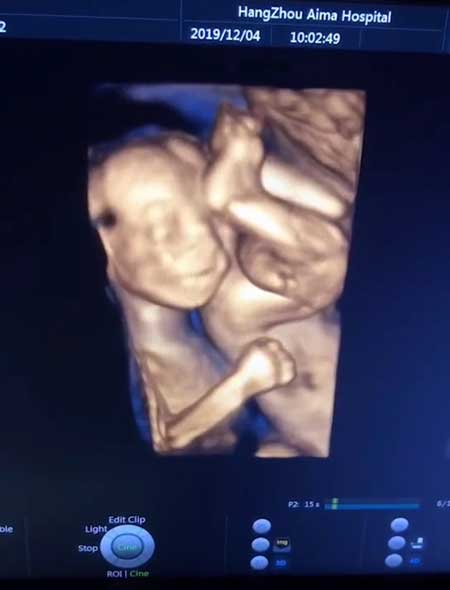

双胎宝贝的表演——弹琵琶!

A:弹起我心爱的土琵琶…

B:同胞,请放开我的PP!

简直太可爱!双胎宝宝在肚子里的有爱互动,都能录下来~

那就在中孕期,通过超声影像来和宝贝“互动”吧:不仅看到宝贝的模样,还可以录下“动态短视频”,让宝宝在出生前就可以有一支自己的Vlog!

在高清成像面前,一举一动都不会错过~

通过超声影像(四维彩超),宝妈们能看到胎宝宝的模样和一举一动,满足了宝妈和家人对宝宝的好奇心理。